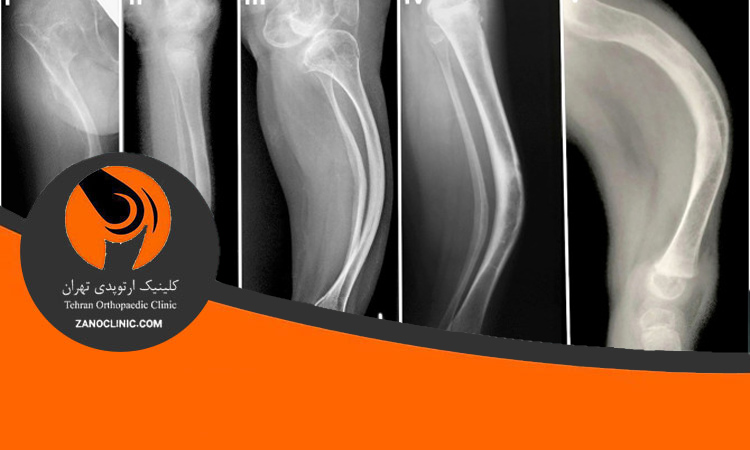

شکستگی استخوان یک حالت پزشکی است که استخوان در برابر استرس و فشار شکست میخورد. تشخیص شکستگی استخوان معمولاً توسط پزشک با استفاده از تاریخچه بیماری، معاینه جسمانی و آزمایشهای تصویربرداری مانند اشعه ایکس و تصویربرداری مغناطیسی صورت میگیرد. در صورت مشکوک بودن به شکستگی، پزشک ممکن است از آزمایشهای تکمیلی مانند آزمایش خون و اسکن استخوان استفاده کند تا تشخیص نهایی را قطعیتر کند. درمان شکستگی استخوان به وابستگی به نوع و شدت شکستگی متغیر است و ممکن است شامل استفاده از چسبها و صفحههای فلزی، برف کشیدن، جراحی و استفاده از مهار کنندهها باشد.

شکستگی استخوان و کال استخوانی میتواند تاثیر بسیاری بر روی کیفیت زندگی فرد داشته باشد، اما با درمان مناسب و به موقع میتوان این مشکل را حل کرد. درمان شکستگی استخوان به دو شیوه اصلی انجام میشود: درمان غیر جراحی و درمان جراحی. درمان غیر جراحی شامل استراحت، استفاده از گچ و فیکساسیون خارجی است. درمان جراحی نیز شامل بازسازی استخوان با استفاده از پینها، پلاکها و مهرهها میشود. انتخاب روش درمان بستگی به نوع و شدت شکستگی استخوان دارد. همچنین برای بهبود درمان و تسریع فرایند بهبودی، فیزیوتراپی و تمرینات مربوطه نیز باید انجام شود. با رعایت و پیروی از دستورات پزشک و فیزیوتراپیست، بیماران میتوانند بهبودی خوبی را در کوتاهترین زمان ممکن تجربه کنند و به فعالیتهای روزمره خود بازگردند.